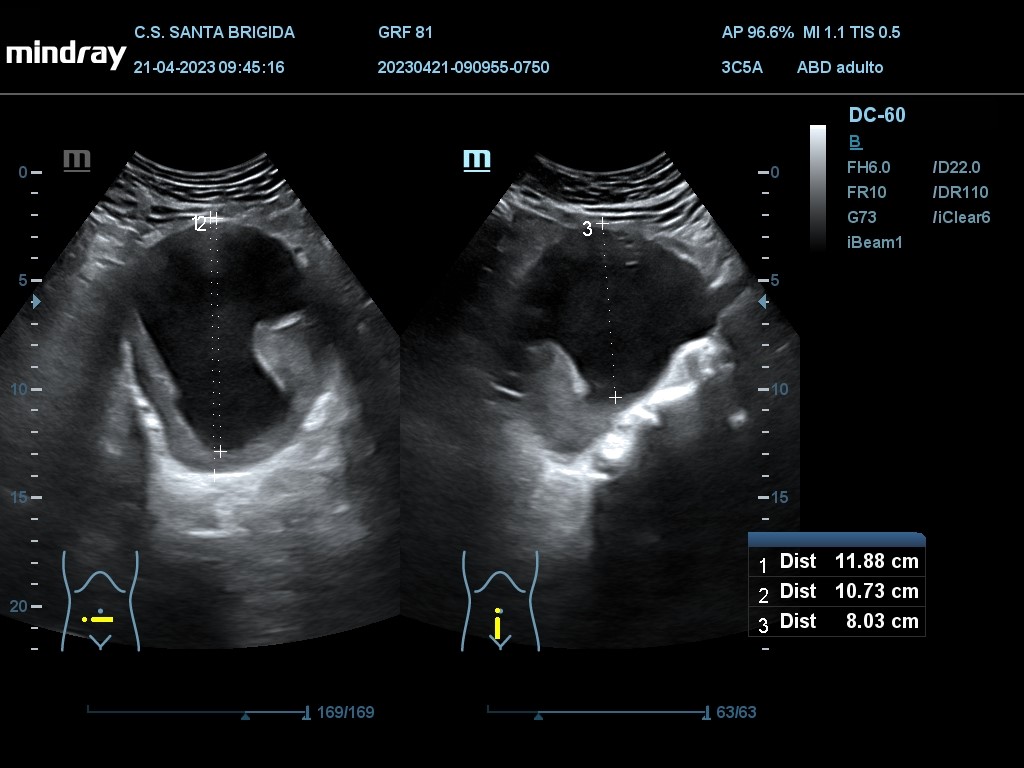

En ecografía clínica se aprecia dilatación de aorta abdominal de extensión máxima de 13,27 cm con origen proximal a la bifuración de las arterias renales y con un diámetro máximo de 9,91 cm. Además asocia imagen hiperecogénica respecto a la luz del vaso en la práctica totalidad de su recorrido en probable relación con trombo intramural semilunar de 3,7 cm.